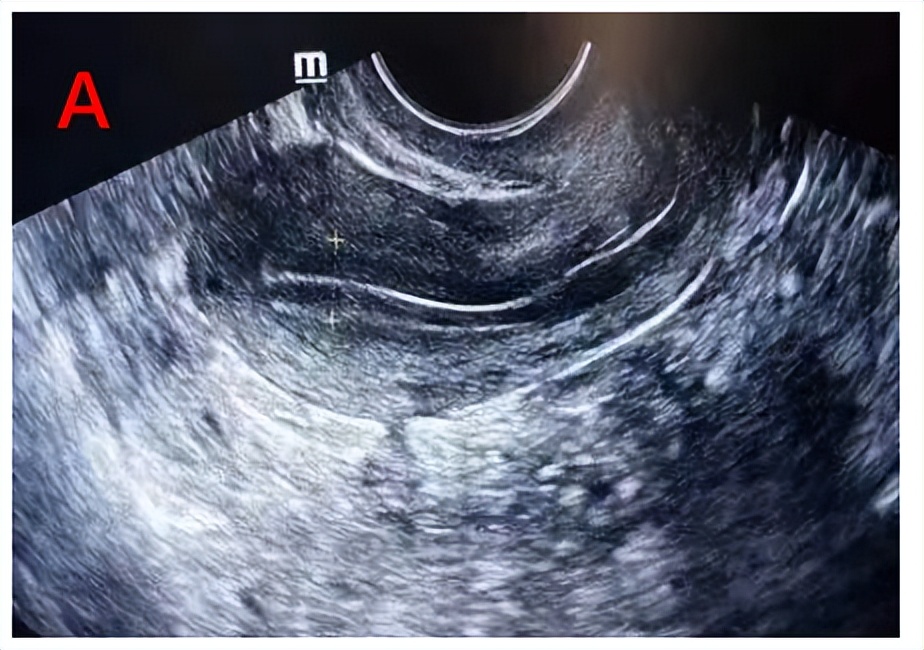

卵泡早期的内膜较薄,厚度约3~6 mm,随着卵泡生长,雌激素水平逐渐升高,内膜不断增厚。当卵泡达到成熟时,内膜厚度一般可达10-14mm。我们利用阴道超声根据Gonen分型标准,对内膜形态进行分型,分为三型:A、B、C型。A型及B型子宫内膜的妊娠率显著高于C型。

A型即三线型内膜,外层和中央为强回声线,外层和宫腔中线间为低回声区。常见于子宫内膜增生期。